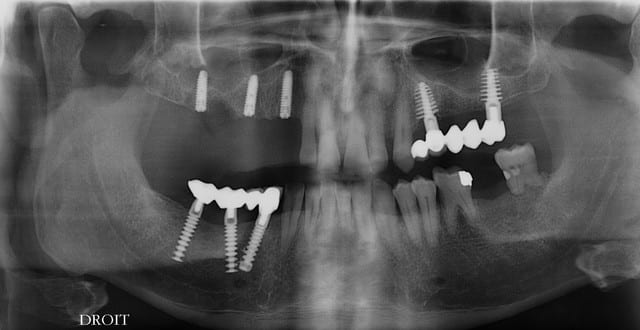

pxav

pano